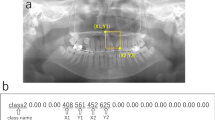

Meary angle is the angle between the long axis of the talus and the first metatarsus. There are many methods to line drawing to represent the long axis of the talus and first metatarsus, but we adopted the method illustrated in Fig. 2a16,17. Meary angle is considered normal within the range of − 4° to 4°, where the angle is defined as positive when the axis of the metatarsus is plantarly tilted less than that of the talus. An angle is less than − 4° is considered PP, and this criterion was adopted as the cut-off value for PP diagnosis2.

A weightbearing lateral radiograph of a normal foot of a 53 year old female, showing measurement of the Meary angle and calcaneal pitch. (a) Meary angle is the angle between the long axis of the talus and the long axis of the first metatarsus. First, the longitudinal axis of the talus is a line drawn through two mid-points. (Green line) One is a mid-point between the cephalad and caudad margins of the talar body, (Longer light green line) and the other is a mid-point between the cephalad and caudad margins of talar neck. (Shorter light green line) The metatarsus axis was determined using the following method. The long axis of the first metatarsus (Yellow line) is drawn by connecting two mid-points equidistant from the cephalad and caudad margins of the first metatarsus at the proximal and distal metaphysial diaphysial junction (blue lines). (b) Calcaneal pitch is the angle formed between the line outlining the inferior border of the calcaneus (yellow line) and the weight bearing surface (green line).

Calcaneal pitch is the angle formed between the line outlining the inferior border of the calcaneus and the weightbearing surface18,19. Generally, the range of calcaneal pitch from 18° to 20° is considered normal and decreased calcaneal pitch is considered PP2. In this study, the angle that is less than 18° was adopted as the cut-off value for PP (Fig. 2b).